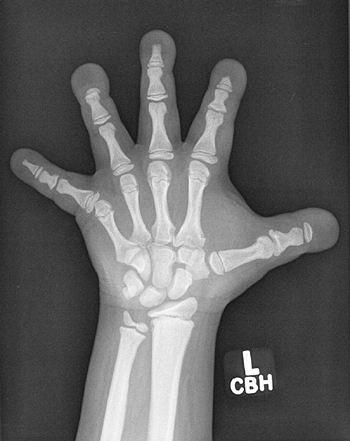

erosions and brown tumors (Fig. 7.5). The

subperiosteal erosions are described as classically appearing on the

radial margins of the middle phalanges of digits 2 and 3 of the hand in

adults. In children, they can also be seen at the lateral aspects of

the distal radius and ulna and at the medial aspect of the proximal

tibia (Fig. 7.6) (123).

Figure 7.6 Renal osteodystrophy in an 8-year-old boy. A:

Radiographs of the hand show sclerosis, acroosteolysis, and soft tissue calcification around the metacarpal phalangeal (MCP) and proximal interphalangeal (PIP) joints. B: Radiographs of the knees show subperiosteal resorption at the medial border of the proximal tibia. |